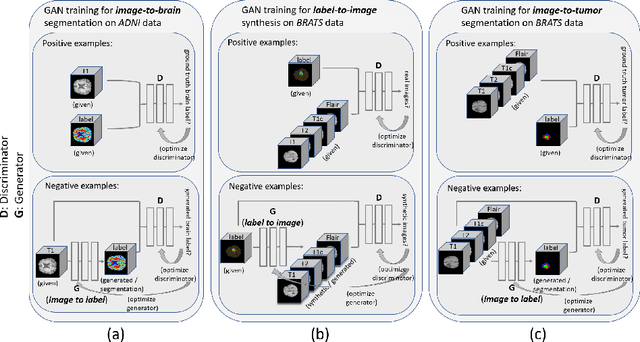

Data diversity is critical to success when training deep learning models. Medical imaging data sets are often imbalanced as pathologic findings are generally rare, which introduces significant challenges when training deep learning models. In this work, we propose a method to generate synthetic abnormal MRI images with brain tumors by training a generative adversarial network using two publicly available data sets of brain MRI. We demonstrate two unique benefits that the synthetic images provide. First, we illustrate improved performance on tumor segmentation by leveraging the synthetic images as a form of data augmentation. Second, we demonstrate the value of generative models as an anonymization tool, achieving comparable tumor segmentation results when trained on the synthetic data versus when trained on real subject data. Together, these results offer a potential solution to two of the largest challenges facing machine learning in medical imaging, namely the small incidence of pathological findings, and the restrictions around sharing of patient data.